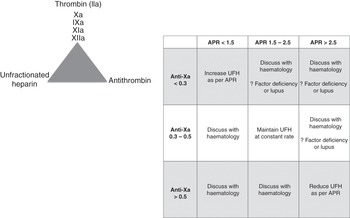

There is no universally agreed therapeutic range. It is a near-patient assay. Most hospitals have not validated their in-house ACT cartridges and do not know how this value correlates with their coagulation tests (which are highly variable from institution to institution). Each hospital should validate the ACT measurements to either their laboratory activated prothrombin time (aPTT) or anti-Xa measures to ensure that the adopted ACT range is at least comparable to the laboratory coagulation tests range. An example is shown in Figure 7.2. The ACT tests will vary in their sensitivity to heparin, and different systems should be used to monitor various clinical settings (e.g. an ACT system designed to be used during cardiac surgery will monitor much higher doses of heparin than systems used during ECMO).

Standard decision trees should be developed to support staff at the bedside. This should include when to call the haematology department (see example in Figure 7.3).

Figure 7.3 Example of a decision tree to support staff at the bedside. VA, veno-arterial; VV, veno-venous; PT, prothrombin time.